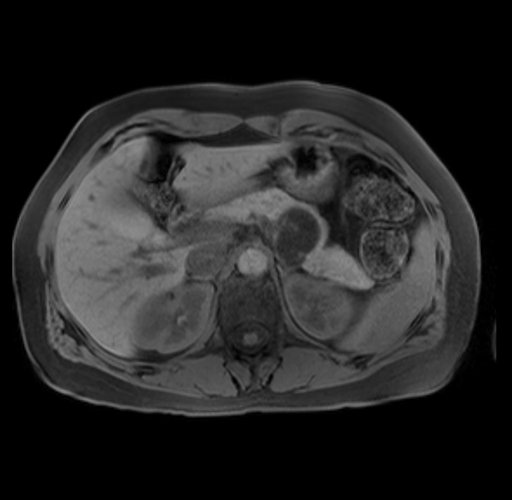

Imaging Analysis

Look through the patient's CT scan to identify any areas of concern for the necessary procedure.

Based on your CT findings, which issue(s) are present and would give reason for "planned slowing down moment(s)" in this case?

Considering a standard distal pancreatectomy procedure, what step(s) of the operation would you do differently in this case?